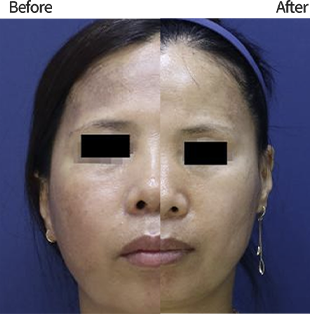

탄력 개선

탄력 개선